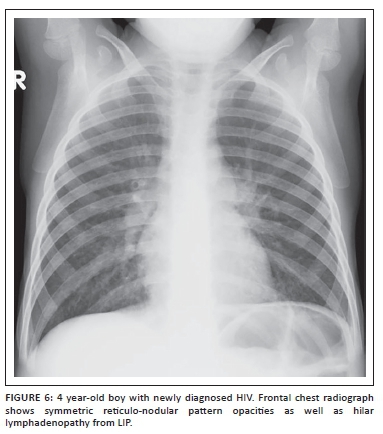

LIP most commonly causes diffuse often symmetrical reticulo-nodular pattern opacities on chest radiographs and CT (Figure 6).5,10,18 The nodules may coalesce to produce areas of confluent airspace opacification (Figure 7).11 Peribronchial thickening alone or cysts and bronchiectasis in long-standing disease may also occur.10,19 Although lymphadenopathy may present in pediatric patients with LIP, it rarely causes tracheobronchial compression which can be often seen in the setting of TB infection.19 It is often difficult to distinguish between LIP and miliary TB on imaging alone. Parotid enlargement as a result of lymphoepithelial cysts, hepatosplenomegaly and digital clubbing are more common in LIP. On HRCT, which may improve the diagnostic accuracy, characteristic perilymphatic and subpleural nodules are often present in pediatric patients with LIP.15